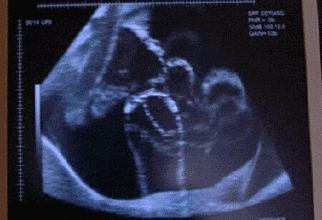

胎动,顾名思义指的就是胎宝在子宫里的活动,但这不单单是胎宝生命的象征,更是孕妈第一次真正感受到胎宝存在的象征。

胎动正常与否,在一定程度上讲,可以说是胎儿是否健康的“晴雨表”。胎动正常则表明胎盘功能良好,输送给胎儿的氧气充足,胎儿在子宫内生长发育健全,如果异常则很可能意味着有问题。不少孕晚期的孕妇都会觉得胎动明显变少了,总是处在担忧中。

在整个孕期中,胎动并不是一直不变的,在各个阶段胎动的情况是不一样的,所以也存在胎动变少的情况。就算胎动变少了,只要胎动依然有规律,有节奏,起伏变化不突兀,就没有多大问题。

到了孕晚期,由于胎儿慢慢长大,胎儿在子宫内的活动范围相对变小,此时的胎动幅度会减弱,所以此时胎动变少了是无需过分担心的。而且不是所有胎儿都喜欢动的,有些宝宝天生较安静,不喜欢乱动而已。如果妈妈一直比较忙碌,没有安静下来,当然就不能一直感受到胎儿的动静,自然就觉得胎动变少了。